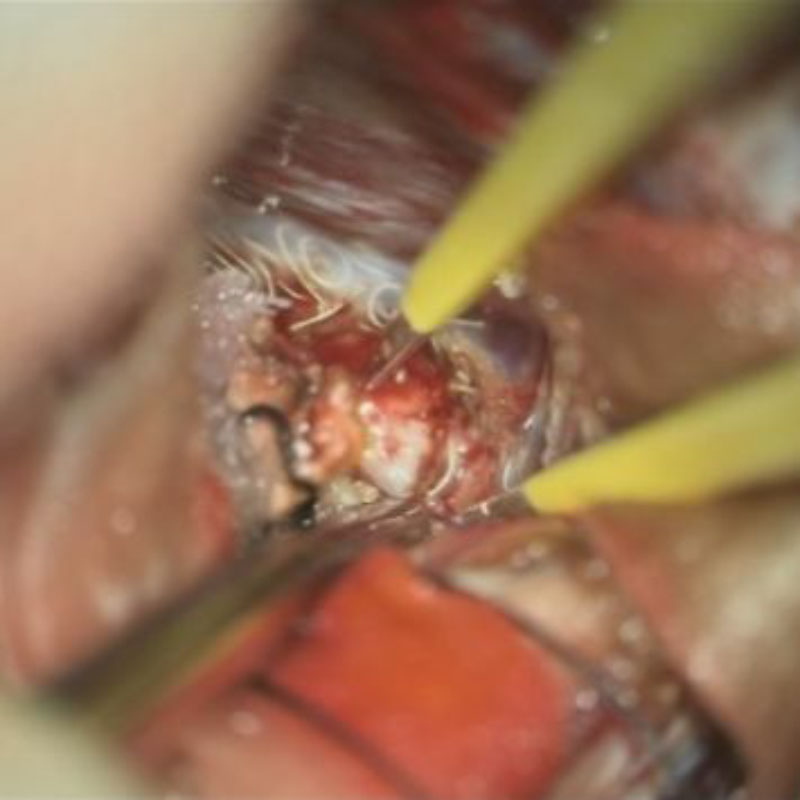

No.452 手術中